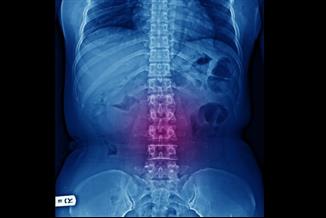

כיצד מונעים כאבי גב באמצעות תרגילים

כאבי גב תוקפים כל אחד ואחת מאיתנו בשלבים השונים של החיים. יש החיים עם כאבי הגב משך כל חייהם. הנה מספר דרכים למניעת או עיכוב התופעה